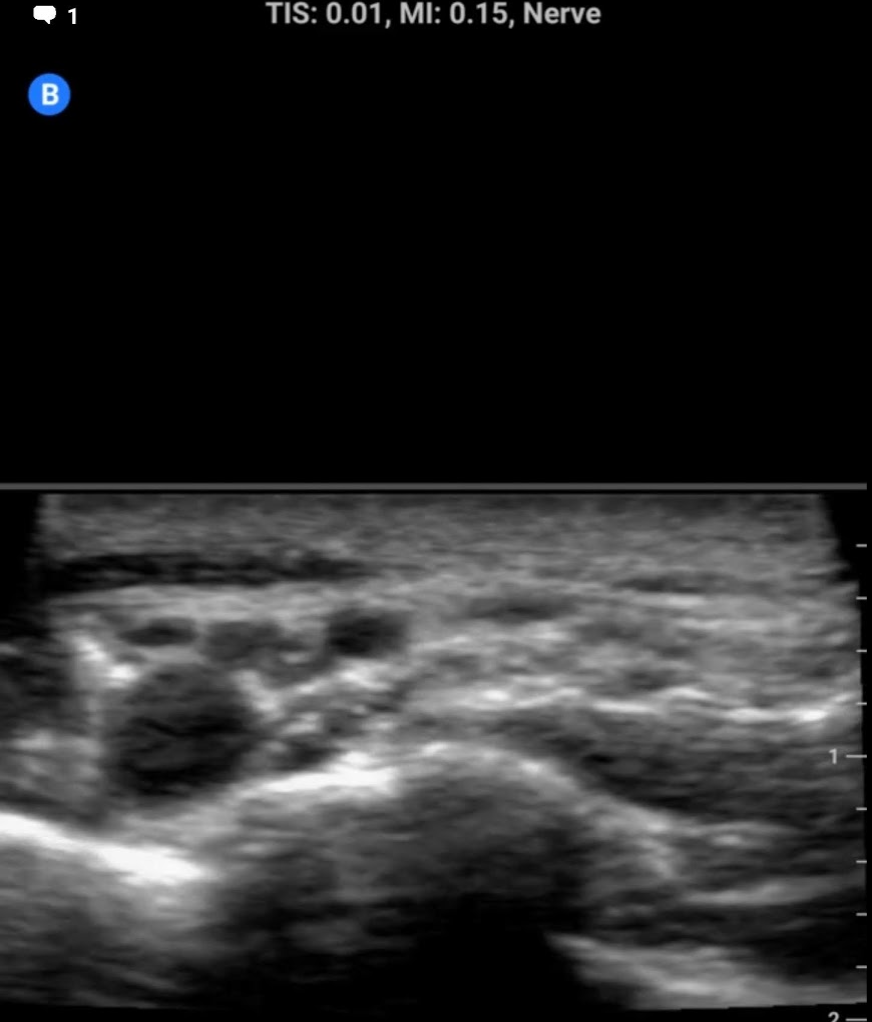

Some sample images below:

screenshot.177.pngscreenshot.178.pngscreenshot.180.pngscreenshot.179.png

View attachment 328368View attachment 328369View attachment 328371View attachment 328372